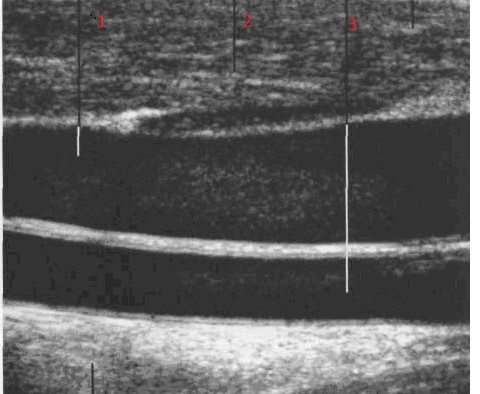

Рис. 25. Сонограмма  щитовидной железы при продольном сканировании: 1- паренхима ЩЖ, 2- внутренняя яремная вена, 3- общая сонная артерия.